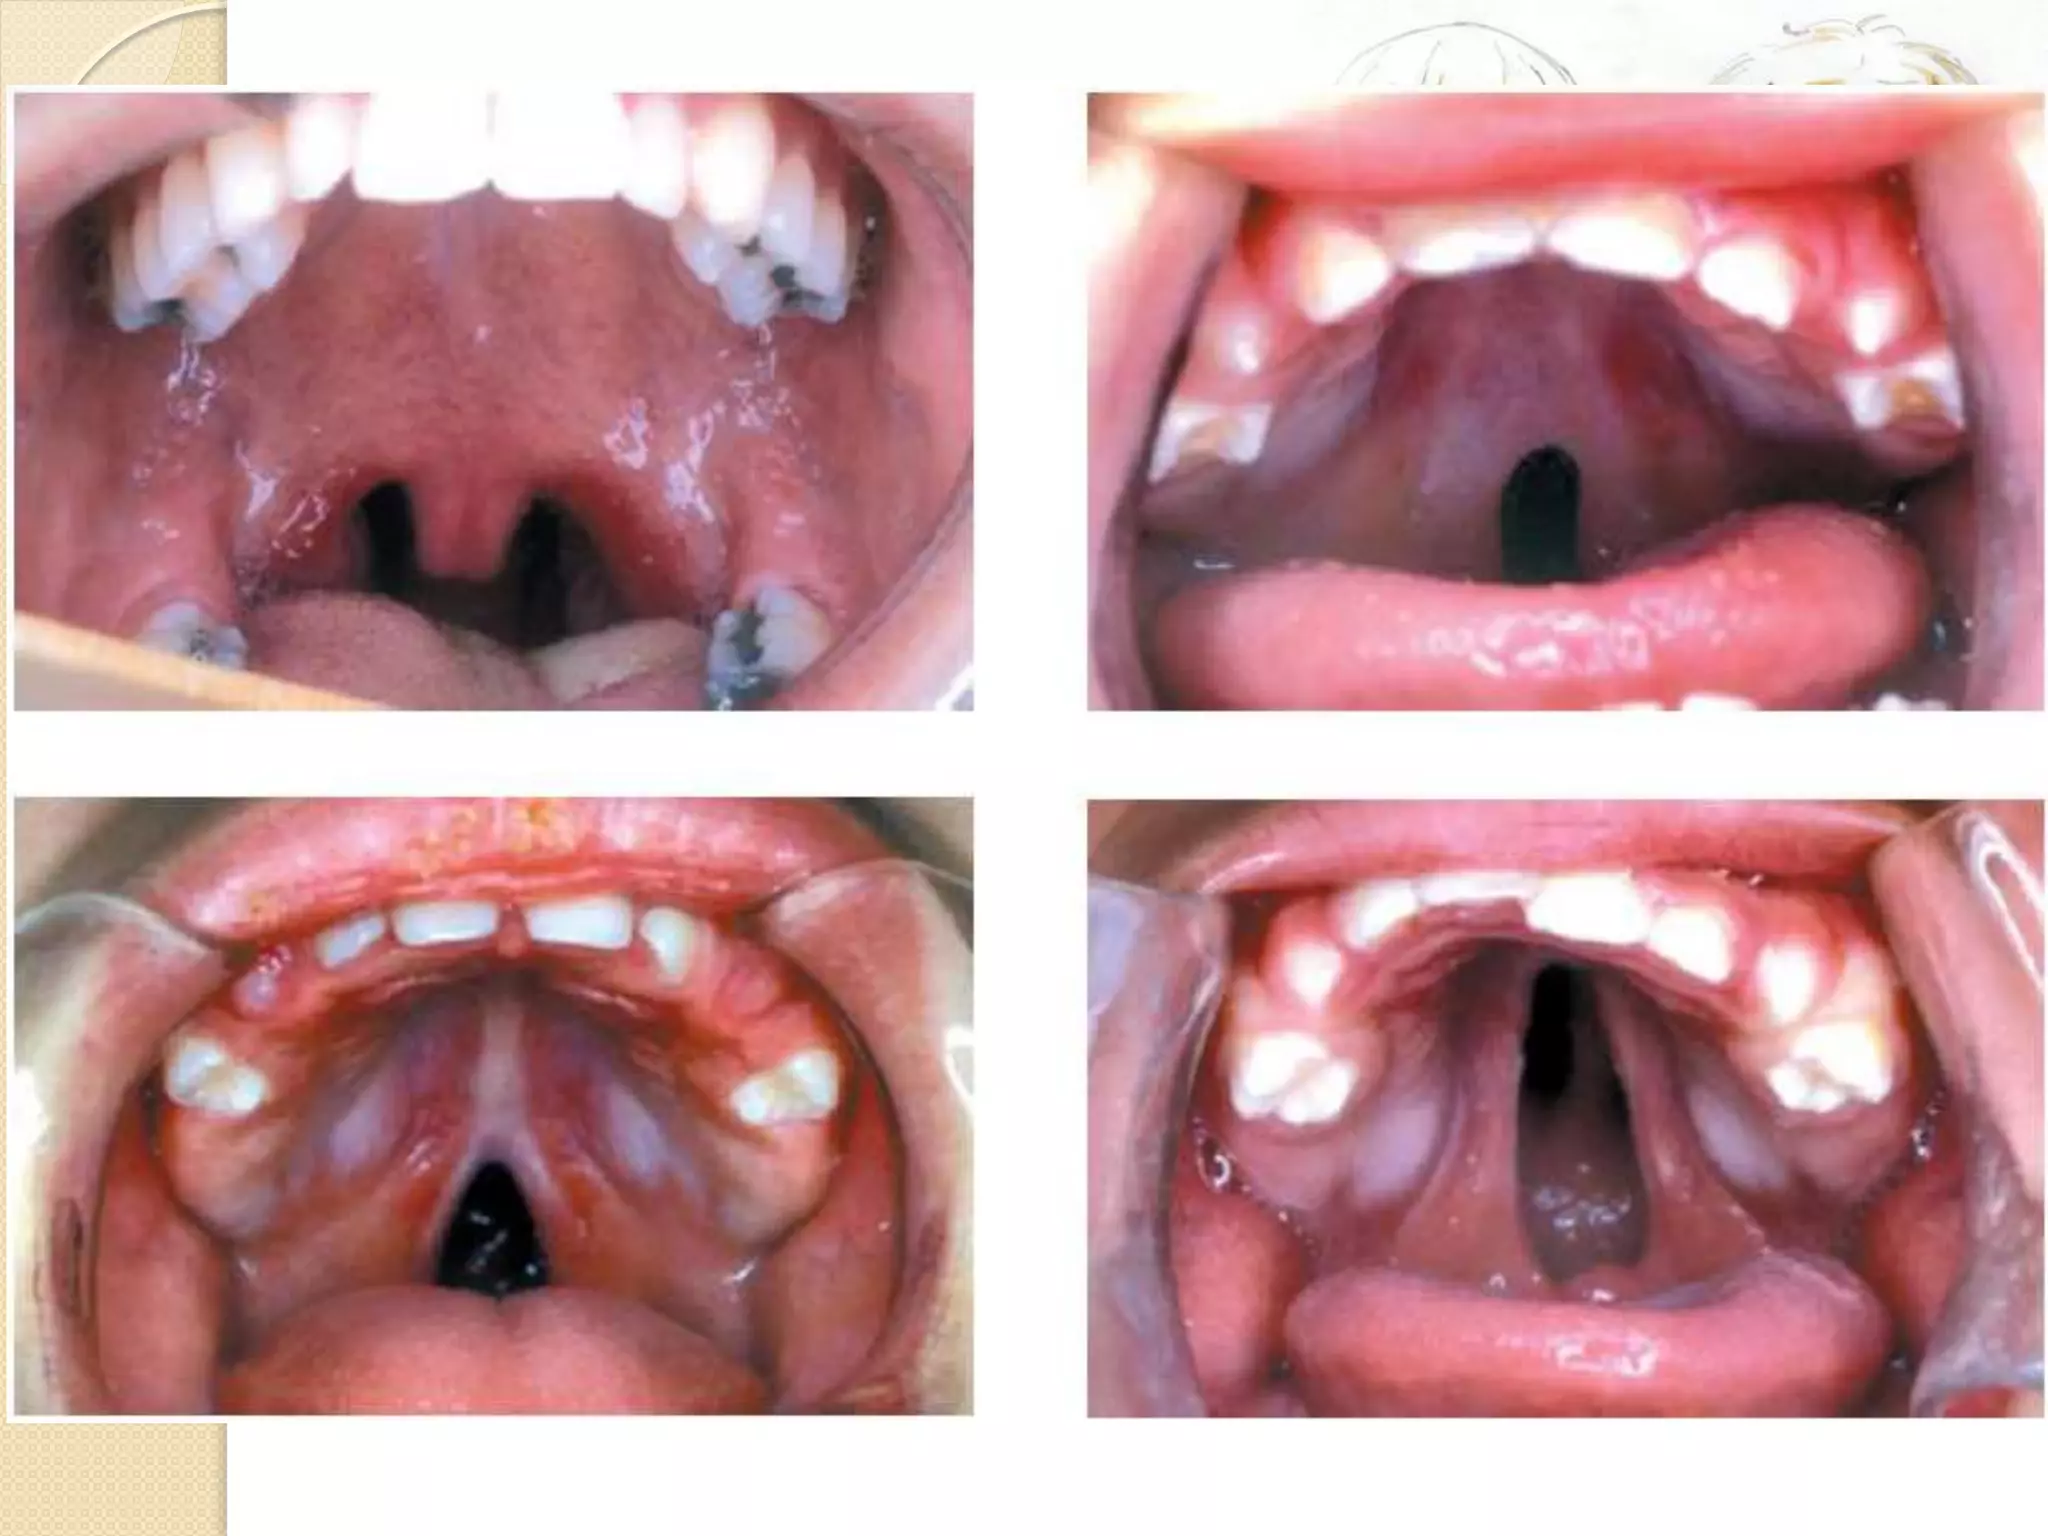

Classification

Classification  Nagpur classification ◦Group I – cleft lip only ◦ Group Ia – cleft lip + cleft alveolus ◦ Group II – cleft palate only ◦ Group III – cleft lip + cleft alveolus + cleft palate

Anatomy

• Philtrum

• Philtral Ridges

• Cupid’s Bow

• Philtral Dimple

• Commisure

• White roll

• Tubercle